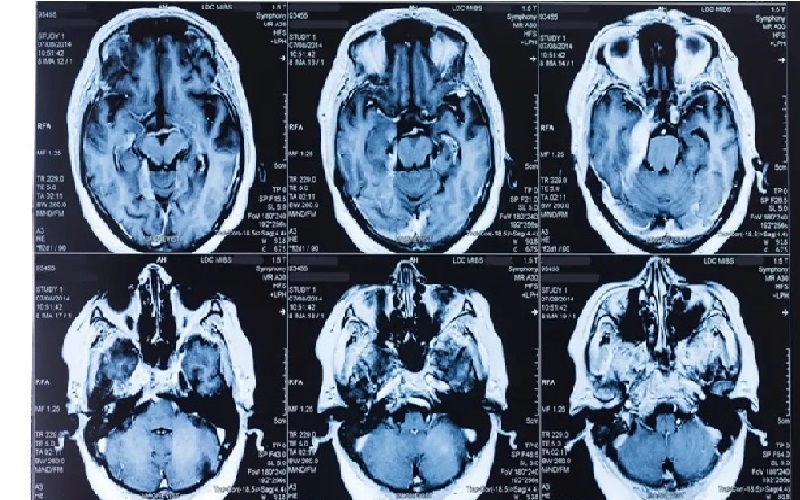

ووفق "نيو ساينتست"، قام الباحث وي شي ليو من جامعة فودان وزملاؤه بتحليل بيانات مسح الدماغ بالرنين المغناطيسي لما يقرب من 11 ألف شخص من سجلات البنك الحيوي البريطاني، والذين تراوحت أعمارهم من 50 إلى 80 عاماً وقت التصوير.

وباستخدام بيانات من 70% من المشاركين، قام فريق ليو بتدريب نموذج ذكاء اصطناعي للتنبؤ بعمر المشاركين بناءً على سمات صور الدماغ، مثل حجم مناطق الدماغ المختلفة وكيف ترتبط الأجزاء المميزة ببعضها البعض.

وعندما تم تطبيق النموذج على الـ 30% الآخرين من المشاركين، كانت تنبؤاته دقيقة في غضون 2.7 سنة من أعمارهم الفعلية.

بعد ذلك، استخدم الباحثون النموذج للتنبؤ بعمر مجموعة منفصلة تضم ما يقرب من 4700 شخص، متوسط أعمارهم 63 عاماً، والذين تم تصوير أدمغتهم أيضًا لصالح البنك الحيوي البريطاني.